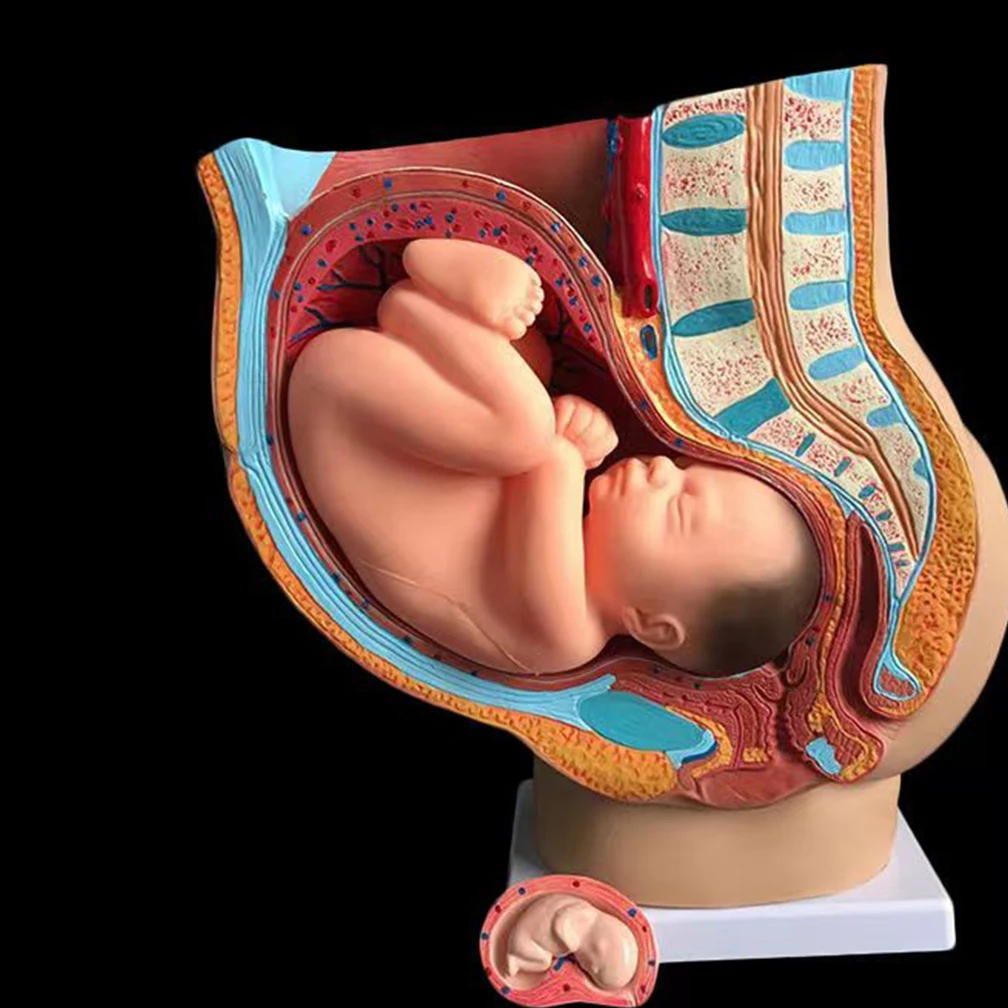

Моменты волшебства: Рождение ребенка в животе мамы

Раздел: Фотозарисовки